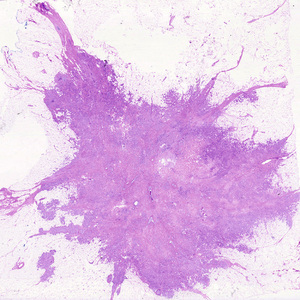

Teratoma is a special type of mixed tumor that contains recognizable mature or immature cells or tissues derived from more than one germ cell layer, and sometimes all three. Teratomas originate from totipotential germ cells such as those that normally reside in the ovary and testis and that are sometimes abnormally present in midline embryonic rests. Germ cells have the capacity to differentiate into any of the cell types found in the adult body; not surprisingly, therefore, they may give rise to neoplasms that contain elements resembling bone, epithelium, muscle, fat, nerve, and other tissues, all thrown together in a helter-skelter fashion.

Malignant neoplasms disseminate by one of three pathways: (1) seeding within body cavities, (2) lymphatic spread, or (3) hematogenous spread. Spread by seeding occurs when neoplasms invade a natural body cavity. This mode of dissemination is particularly characteristic of cancers of the ovary, which often cover the peritoneal surfaces widely. The implants literally may glaze all peritoneal surfaces and yet not invade the underlying tissues. Here is an instance where the ability to reimplant and grow at sites distant from the primary tumor seems to be separable from the capacity to invade. Neoplasms of the central nervous system, such as a medulloblastoma or ependymoma, may penetrate the cerebral ventricles and be carried by the cerebrospinal fluid to reimplant on the meningeal surfaces, either within the brain or in the spinal cord.